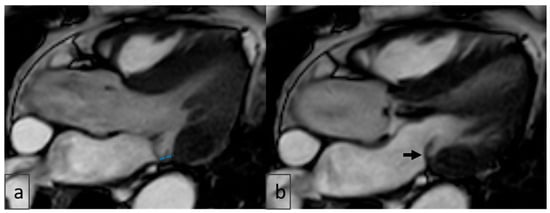

2.4. Image Analysis

3.6. Cardiac MRI Findings in MAD

3.10. Additional Imaging Findings